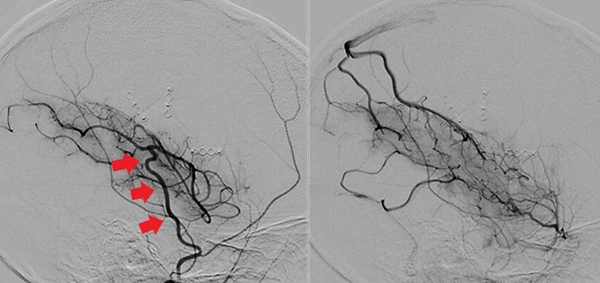

Caso clínico # 2: LD femenino de 51 años con antecedente de tabaquismo e hipertensión arterial, estudiada por deterioro cognitivo de varios meses de evolución. La RMN y ARM evidencia atrofia de hemisferio cerebral izquierdo con hiperintensidad periventricular y disminución franca del calibre de las arterias cerebral anterior y media izquierda con desarrollo de los vasos de MM (Fig. 3). La ADC muestra el stop de la arteria carótida interna izquierda distal y ausencia del origen de las cerebrales anterior y media, buen desarrollo de los vasos de MM y aporte de vasos meníngeos y etmoidales correspondiente a un grado 4 de Suzuki (Fig. 4). Se realizó una revascularización cerebral combinada: un bpTS izquierdo más EDMS y, para aumentar la perfusión en territorio de ambas arterias cerebrales anteriores, un EGPS bifrontal. En la TAC postoperatoria se evidenció un infarto fronto-polar mesial sin repercusión clínica. La ADC postoperatoria diferida evidencia una buena revascularización en los territorios de las arterias cerebral anterior y media a partir del bpTS y la doble sinangiosis (Fig. 5).

Fig. 4 Caso clínico # 2. ADC preoperatoria con compromiso bilateral de las arterias carótidas supraclinoidea mayor a izquierda, vasos de MM y presencia de anastomosis leptomeníngeas. Nótese el signo de la botella de champagne en el origen de la arteria carótida interna cervical, presente en los MM avanzados. Corresponde a un grado 4 de Suzuki

Fig. 5 Caso clínico # 2. Postoperatorio. A la izquierda una TAC con pequeño infarto frontomesial. La imagen del centro es una ADC de frente que muestra el bpTS con muy buena perfusión cerebral. La imagen de la derecha es la ADC de perfil que muestra una buena perfusión cerebral a partir de la EGPS bifrontal